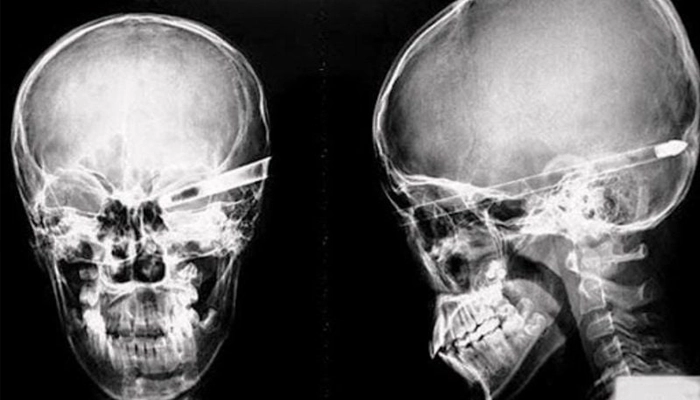

4.2. Chẩn đoán hình ảnh

Chụp X-quang sọ: Phát hiện vùng mất xương, mỏng xương hoặc biến dạng xương sọ.